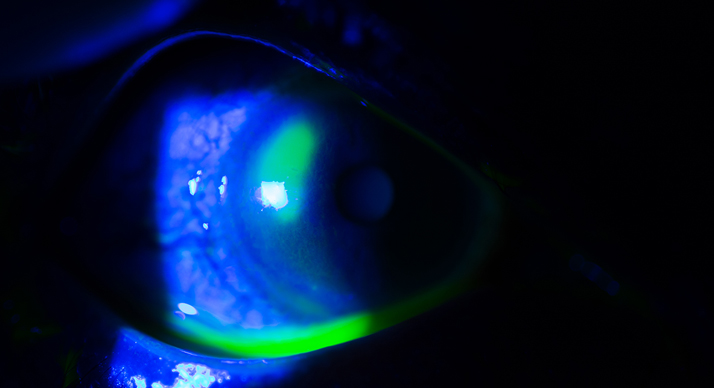

Lesões na córnea que geralmente causam dor e turvação visual. Se não tratadas podem cursar com perfuração e/ou extensão do processo infeccioso (quando o caso) para dentro do olho.

As principais causas são Infecções e processos Imunológicos.